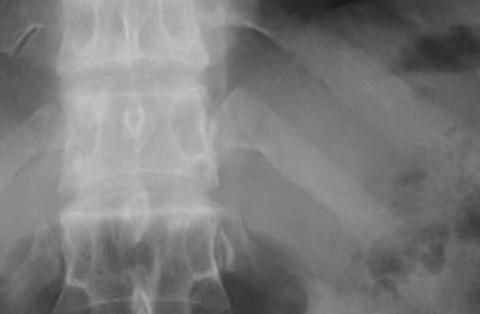

自分の肘が脇腹に入り余りの痛さに病院へ→レントゲン撮ると肋骨ちょびっと骨折だった。

「今から絶対安静です!内臓(脾臓)破裂してたので緊急手術です」と言われた。

内出血で2L以上出ており(致死量近い)危険な状態で身内の血液型を聞かれた。

「内臓破裂ならともかく大げさなww、もっとも破裂してたらこんなもんじゃない」

2日後に退院しろと言われましたが看護士さんがCT撮るべきです!って言ってくれて

「気が済むんなら撮れば?」って内臓破裂発覚。